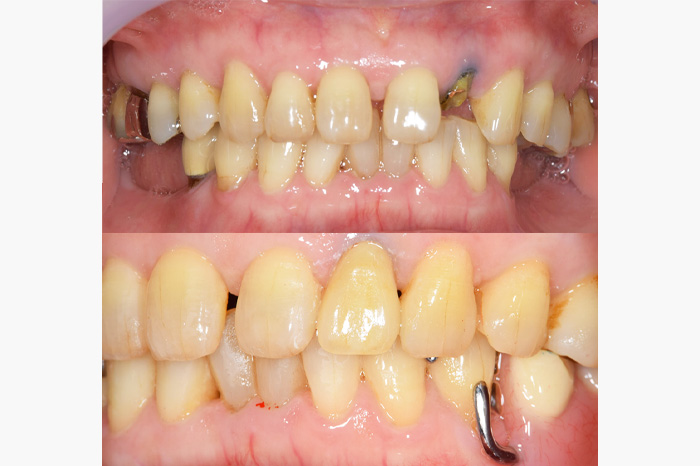

| 年齢 | 70代・女性 |

|---|---|

| 主訴 | 前歯が取れた |

| 治療内容 | 前歯部MTMと同時に審美面の回復。 MTM中に義歯の作成も同時に行う。 最終的に義歯と前歯のクラウンを同時にいれる。 義歯は下顎で、しっかり噛めること、違和感の少ないものという希望があったため、なるべく入れ歯を薄く作成するために金属をしようした義歯とした。 また、見た目もあまり義歯が目立たない様に、バネの部分を見えにくいように作成した。 |

| 治療費 | MTM:110,000円(税込) ファイバーコア:16,500円(税込) E-maxクラウン:110,000円(税込) 義歯:660,000円(税込) |

| 治療期間 | 8ヶ月 |

| リスク・副作用 | 歯にもともと入っていた金属の種類によっては、歯自体の変色を治療で変えられないこともあります。 義歯は作ってから痛みがでることがありますが、それは調整を行うことで痛くなくすることができます。 |